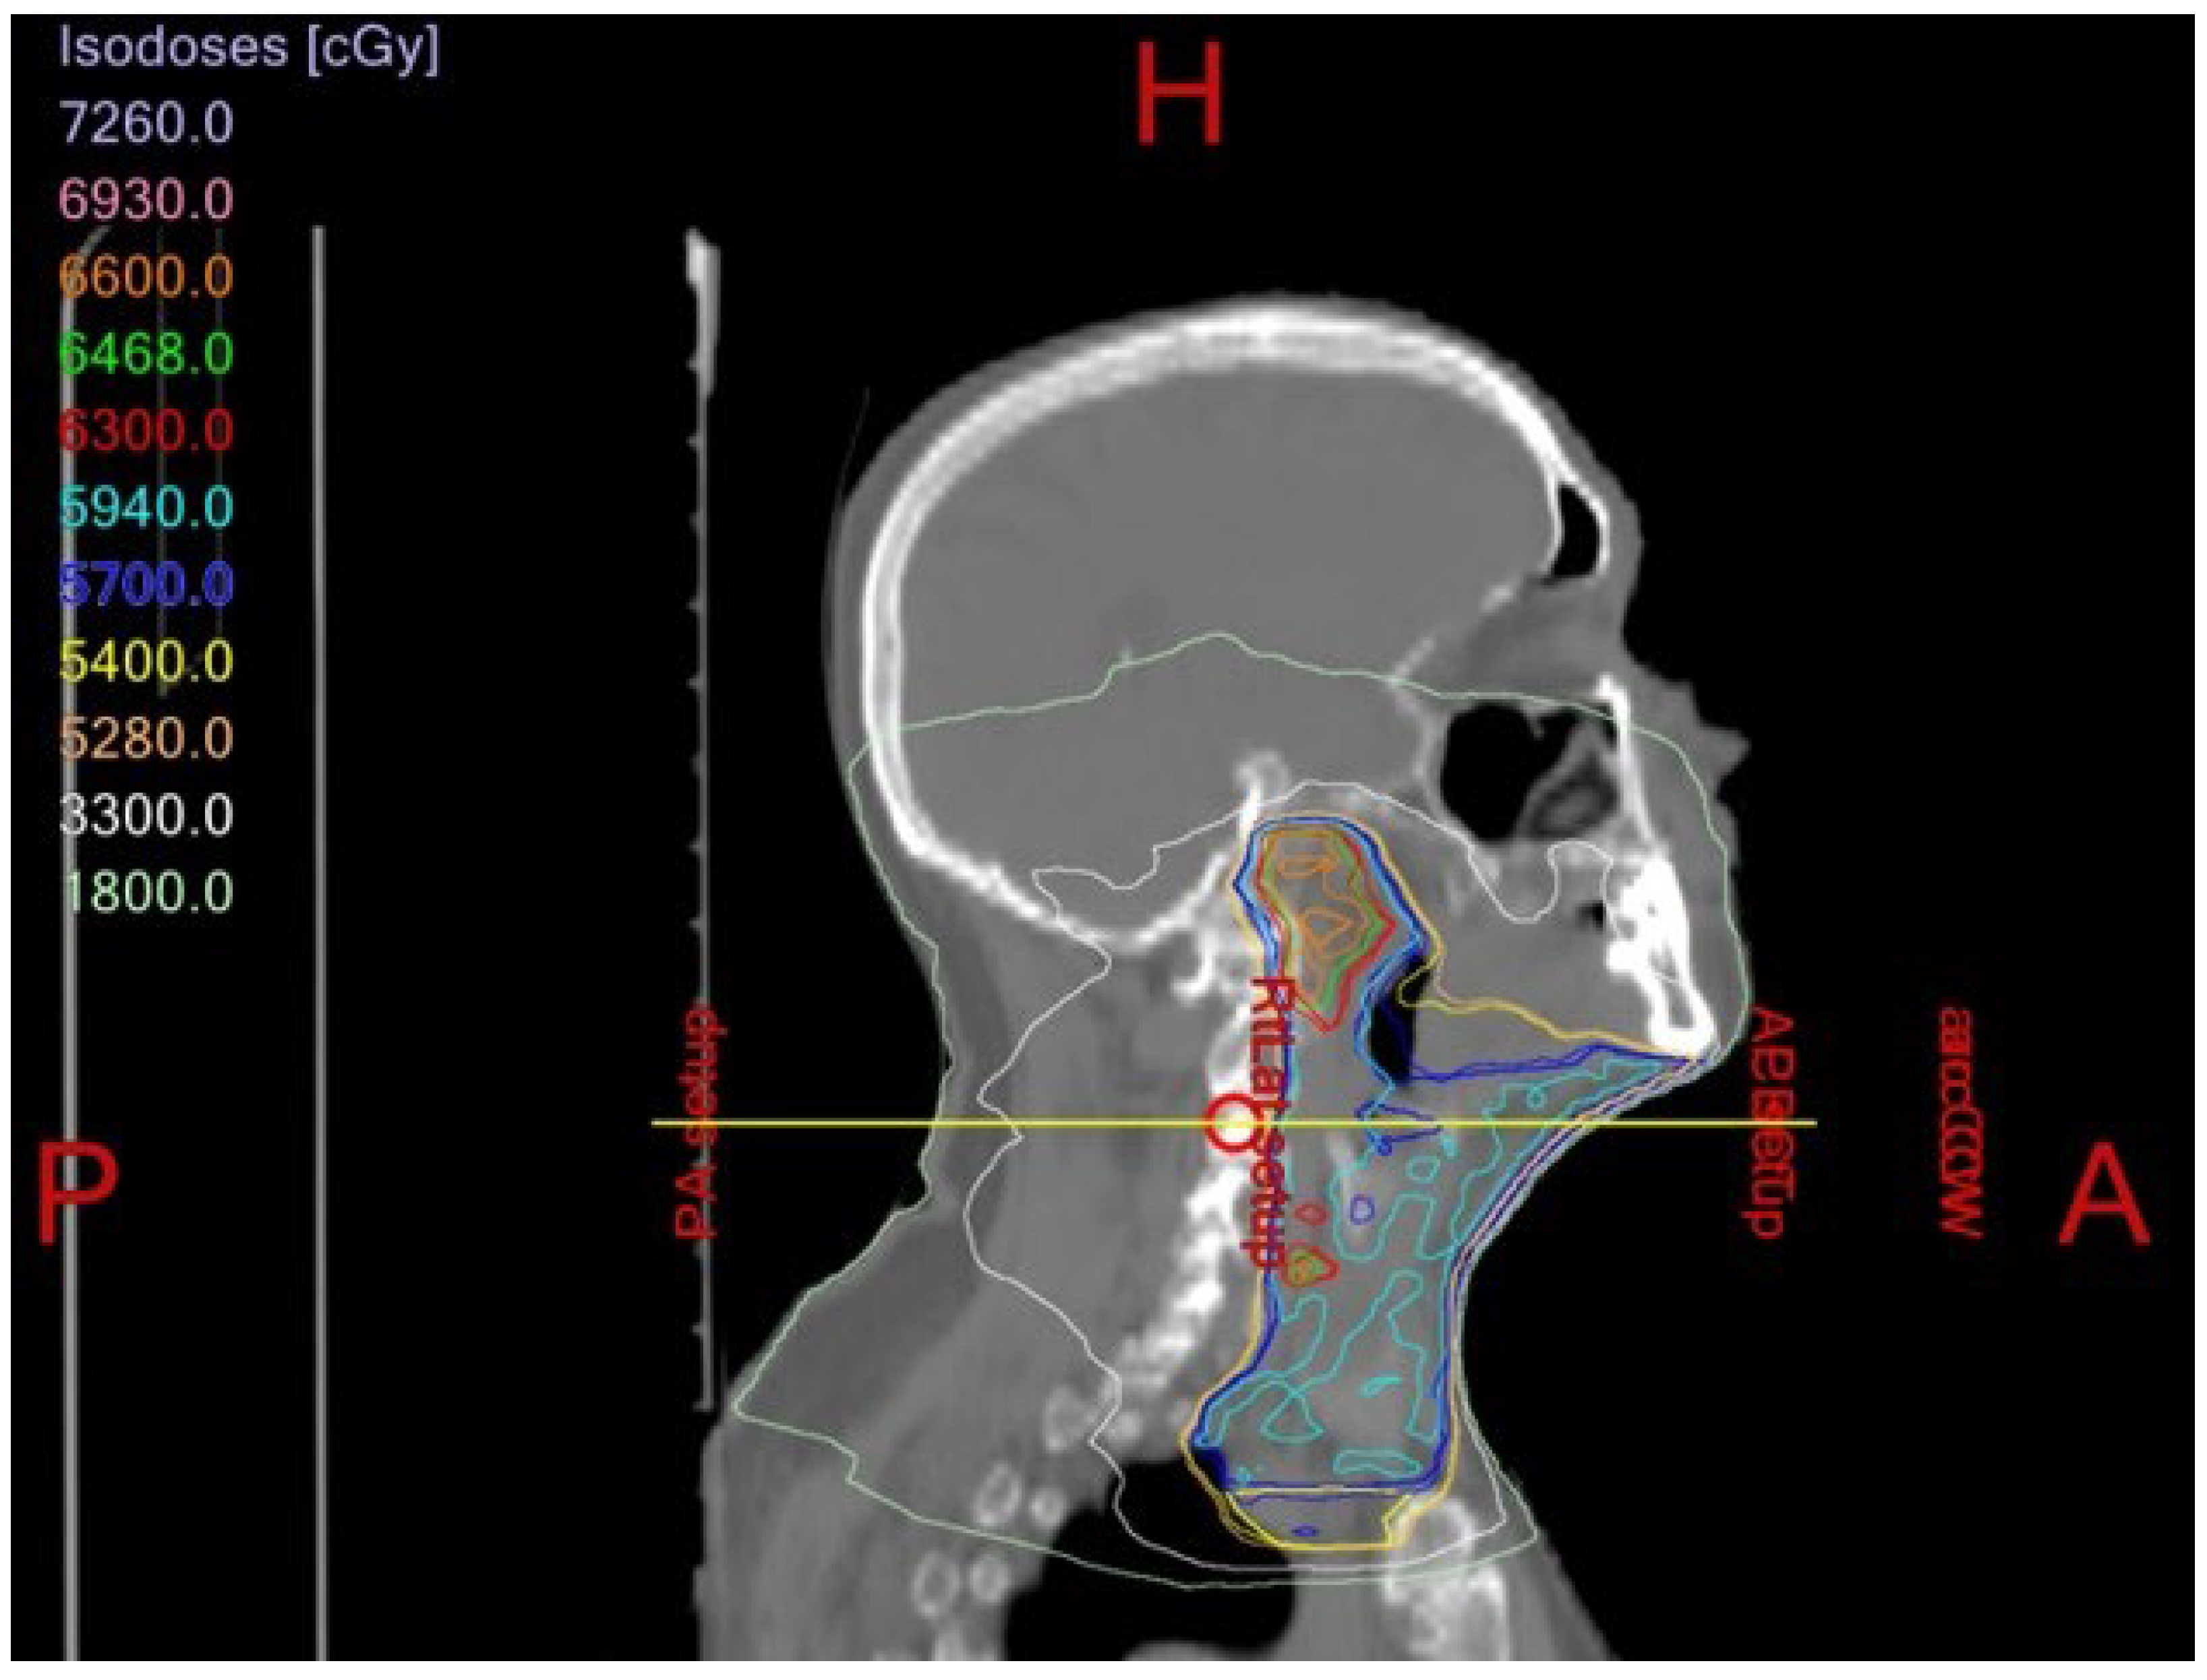

- Romesser, P.B.; Cahlon, O.; Scher, E.; Zhou, Y.; Berry, S.L.; Rybkin, A.; Sine, K.M.; Tang, S.; Sherman, E.J.; Wong, R.; et al. Proton beam radiation therapy results in significantly reduced toxicity compared with intensity-modulated radiation therapy for head and neck tumors that require ipsilateral radiation. Radiother. Oncol. 2016, 118, 286–292. [Google Scholar] [CrossRef] [PubMed]

- Owosho, A.A.; Yom, S.K.; Han, Z.; Sine, K.; Lee, N.Y.; Huryn, J.M.; Estilo, C.L. Comparison of mean radiation dose and dosimetric distribution to tooth-bearing regions of the mandible associated with proton beam radiation therapy and intensity-modulated radiation therapy for ipsilateral head and neck tumor. Oral Surg. Oral Med. Oral Pathol. Oral Radiol. 2016, 122, 566–571. [Google Scholar] [CrossRef]